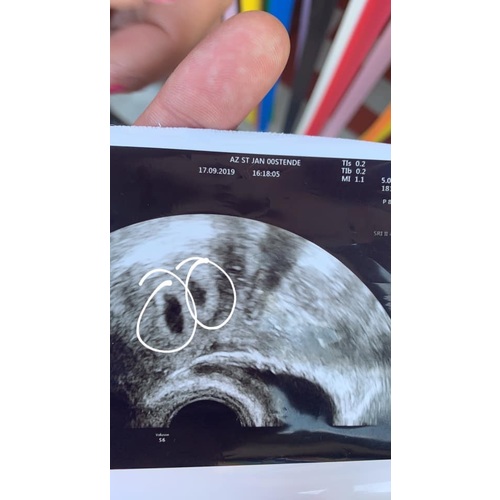

Dit konden wij zien op 5weken 4dagen.

Op de echo zelf zagen wij wel de vruchtzakjes al.